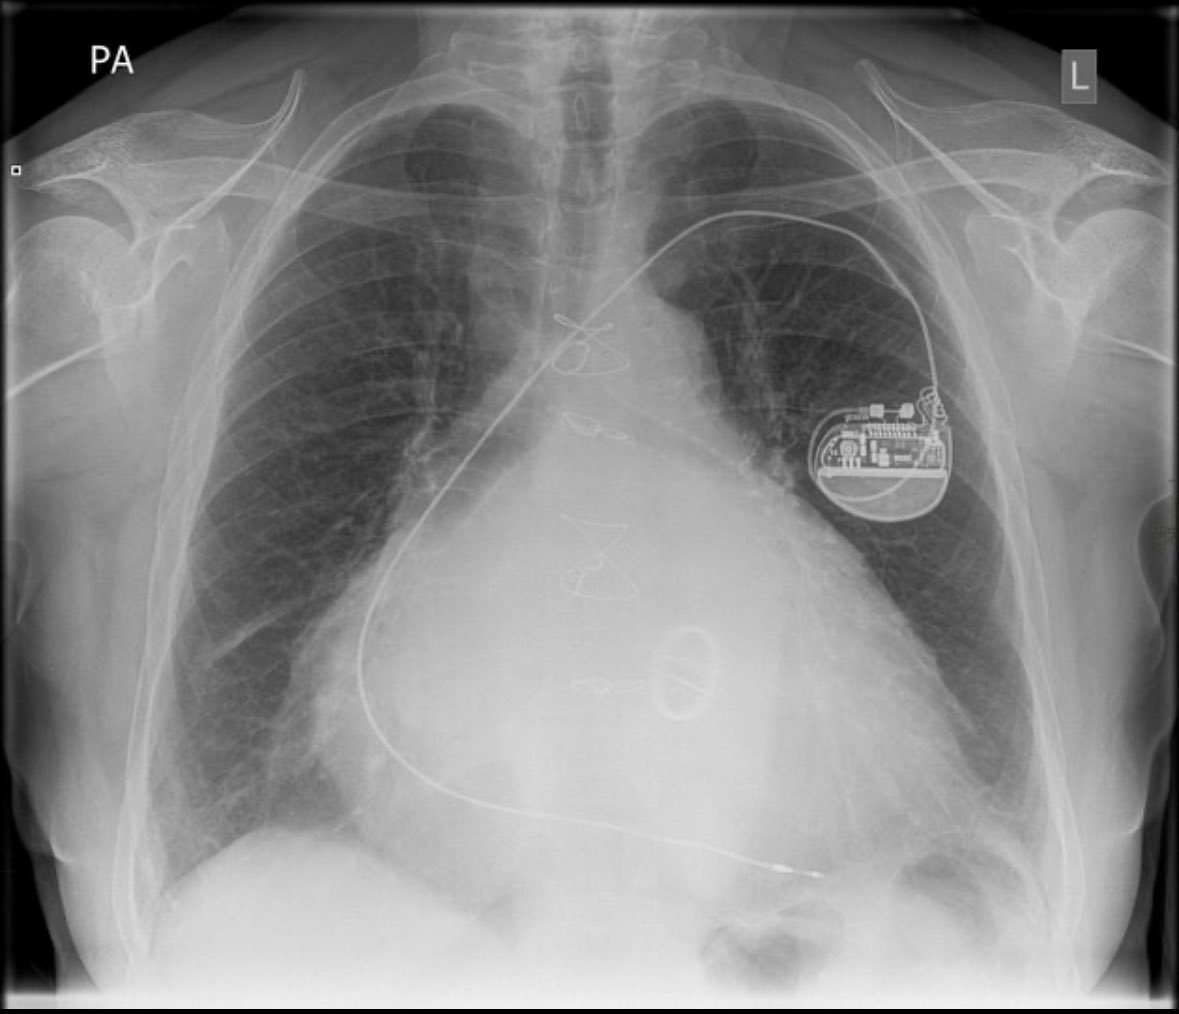

Recently indexed in PubMed, JICRM welcomes original research, research review, and case studies on topics affecting cardiac EP clinical practice today. No reader, author, or submission fees. Submit manuscript for review: bit.ly/2ZcAYDx #Epeeps #cardiotwitter #medtwitter